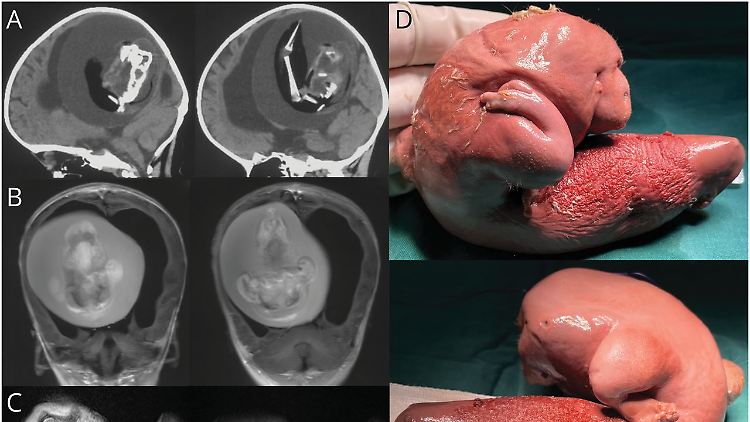

Auf den Fotos sieht man die Anlage von Extremitäten und Fingern.

(Foto: American Academy of Neurology)

Die Einjährige wurde wegen motorischer Verzögerungen und einem vergrößertem Kopfumfang in ein Krankenhaus gebracht und dort untersucht. Die Ärzte machten mit Computertomografen Aufnahmen von ihrem Kopf und sahen bereits in diesen Aufnahmen einen fötusähnlichen Einschluss, den sie in einer anschließenden Operation entfernten, untersuchten und genetisch analysierten. Sie stellten dabei fest, dass es sich tatsächlich um einen Fötus handelte, der genetisch ein Zwilling des Mädchens war.